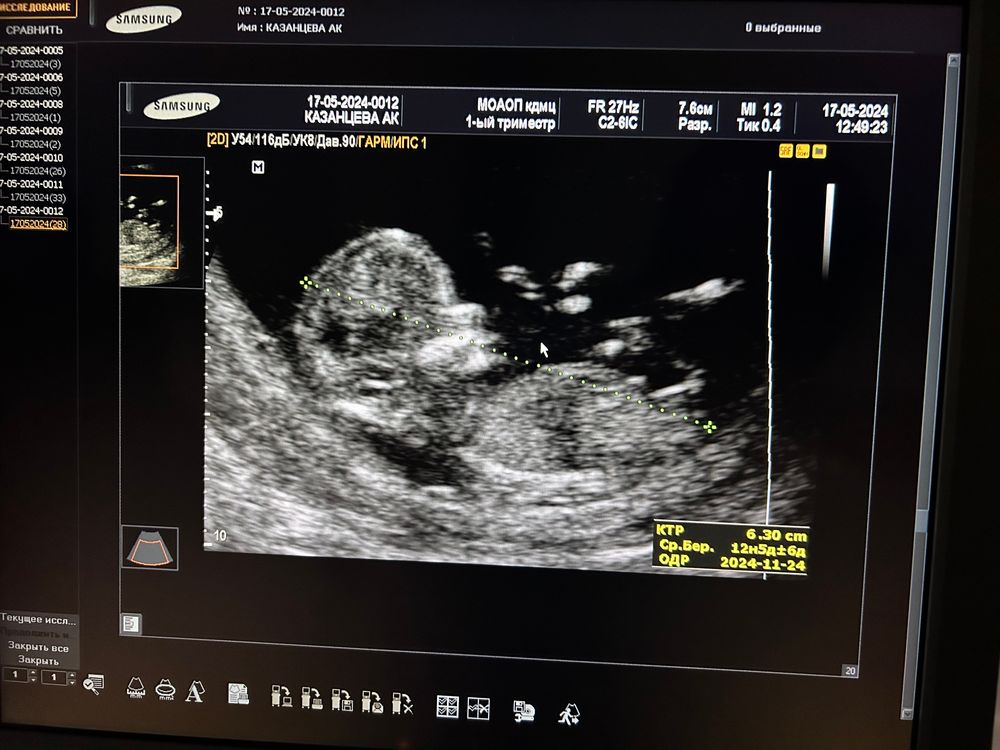

Первый скрининг

Очень на девочку похожа по бугорку

Привет) Мои поздравления ❤️🫂 И у меня пдр 24.11. 😌

Поздравляю )))) у меня пдр такая же дата ) сегодня с мужеи были на узи (14 был скриниг, но мне ничего не показали) я просто ради интереса пол спросила, мне сказали, что ничего не видно, но предположительно, по чсс (150) - девочка )

FF, спасибо и вас, идем нога в ногу😄 а по чсс как? У меня 165

Аделина , спасибо))) узистка сказала, что у мальчиков чсс выше, больше 160. Но это все равно не точно))))) первый чсс, который мы замеряли был 178